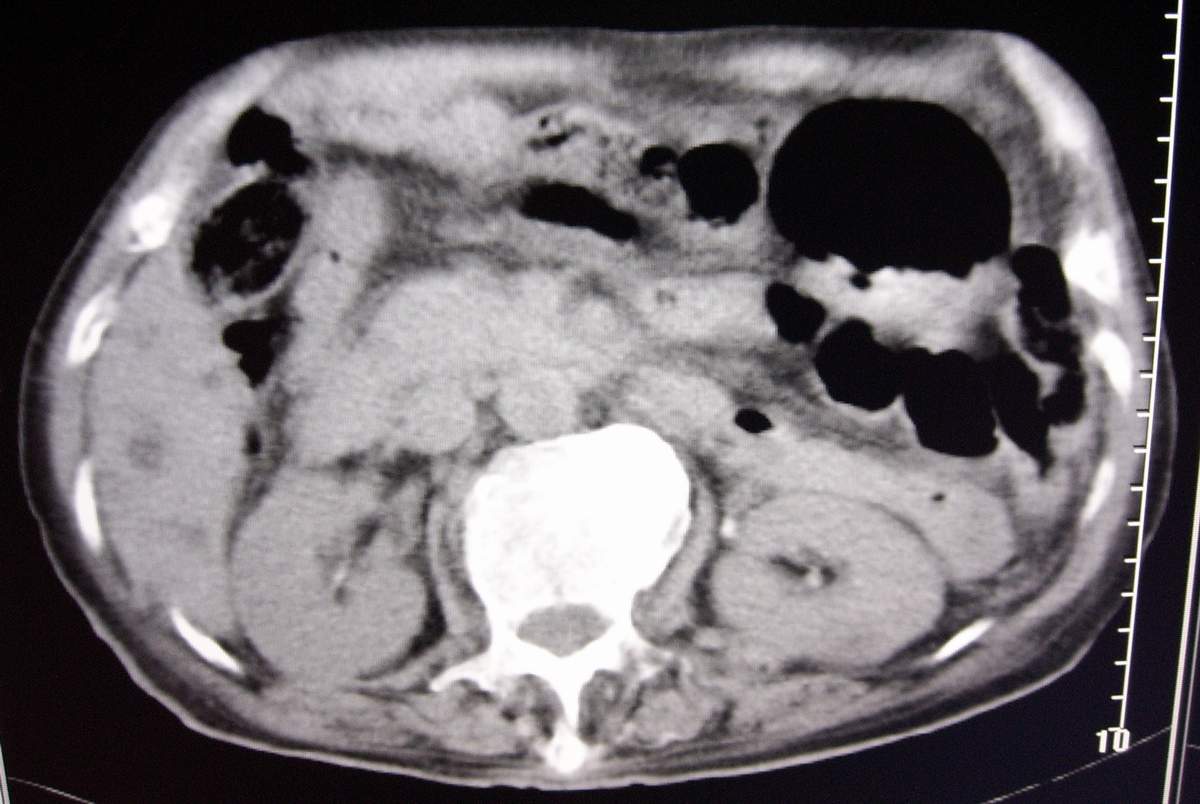

男,77岁,病史不详。

肝内胆管扩张、主胰管扩张 ,胰头影大,考虑胰头癌或胆管下端癌侵犯胰腺可能性大

另外见:胆囊结石 左肾囊肿

肝内外胆管明显扩张,但是程度较轻,应该是个慢性的过程,增强扫描后未见明显异常强化,胰管增宽、扩张考虑为胰头部占位性病变。

慢性胆囊炎,胆结石,左肾囊肿,胰头癌伴肝内胆管、胰管扩张,不除外侵犯肠系膜上静脉的可能。

肝内胆管普遍扩张,呈串珠状改变,走行不规则,且右叶胆管周围肝实质密度呈条片状减低,未见占位性病变,外周胆管及胰管扩张不及肝内胆管.胰腺钩突形态正常,胰十二指肠区域未见明显结节及肿块,初步考虑慢性胆管炎可能性大.请结合临床病史.另外用宽窗看一下吉氏筋膜有无增厚.

1 肝内外胆管扩张,肝内明显,胰管扩张,胰头明显增大,符合胰头癌双管征。2 胆囊壁略增厚,胆囊内可见高密度结石影,胆囊炎、胆结石3 左肾囊肿